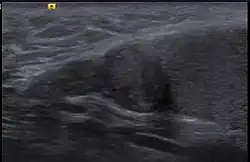

Imaging

In order to see adenomatoid tumors multiple imaging modalities are used. These tumors appear to be small, solid, and circumscribed with a color that usually ranges from white to tan.[6]

Ultrasound, MRI, and CT scans are all used to identify whether a patient has adenomatoid tumors. The shape, location, and activity of the tumor are all important information to attain. Each imaging modality has its own strengths and weaknesses. Dynamic contrast enhanced MRI can differentiate tumors from disorders in the testicular region. Misdiagnosing something can sometimes cause more damage then doing nothing. One weakness of adenomatoid tumor ultrasound imaging is that it is only possible if the tumor is hyperechoic. Ultrasonically can help identify if it fits this category or not. This specific characteristic in adenomatoid tumors is variable and can determine whether or not ultrasound is the right technique for the job.[11] Having other options available to identify the tumor helps fill in the gap when ultrasound is not possible. MRI and CT imaging are usually helpful when scanning the adrenal gland for tumors.[12]